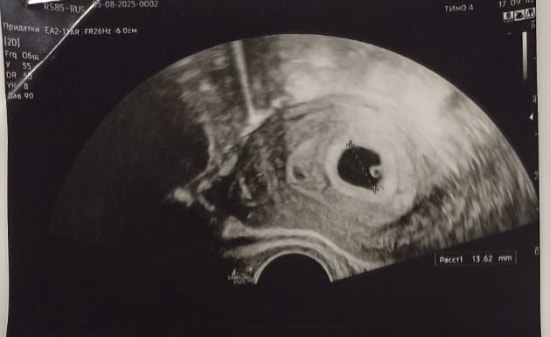

Ольга , ну я была неделю назад. У меня моя бусинка была хорошо видна). Но хотелось бы СБ услышать и убедиться, что все хорошо. Сегодня у меня 6 акушерских недель 6 дней. По-идее должно уже быть СБ сегодня, а завтра я записана на учет. Поэтому и решила сегодня сходить. Тут 5 недель 4 дня. Изображение